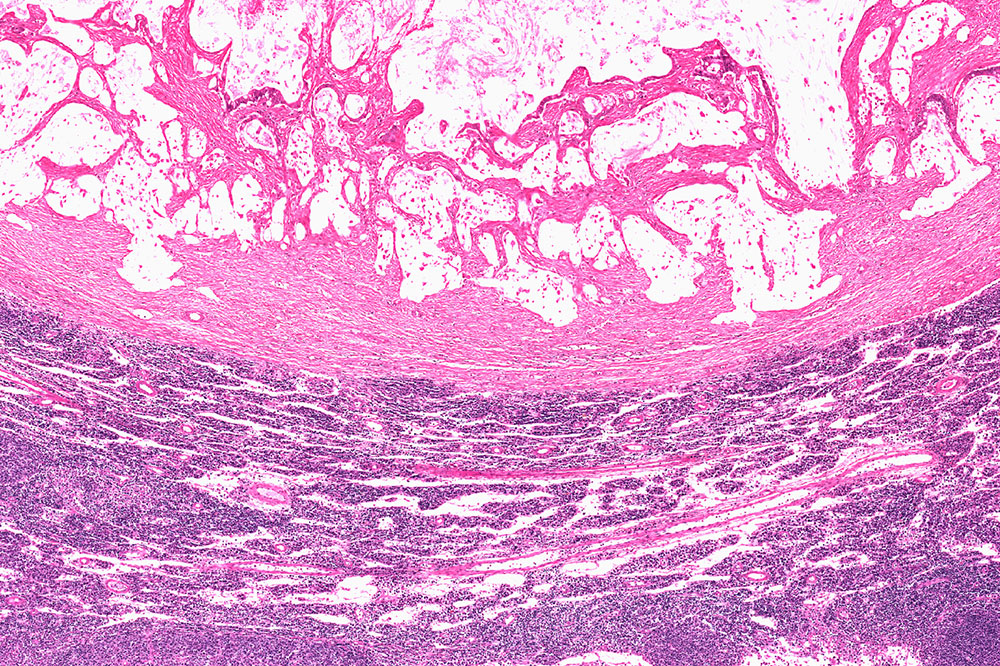

Gastrointestinal Stromal Tumor (GIST) occurs when the body abnormally grows cells in the gastrointestinal linings. These abnormally growing cells have the potential to develop into cancer and must therefore be treated as early as possible. This type of growth can be observed anywhere along the digestive tract, but it is most commonly observed in the stomach and small intestine.

The abnormal growth of cells associated with GIST is typically observed in special cells in the body known as interstitial cells of Cajal (ICCs).